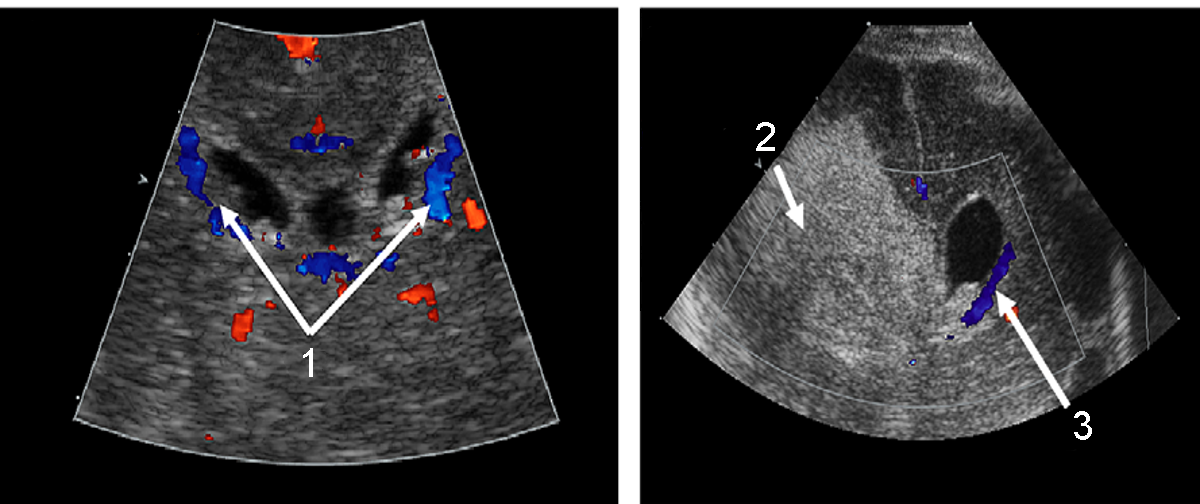

Neonatology PVHI Coronal View Doppler Image

1. Terminal Vein

2. Periventricular Venous Hemorrhagic Infarction (PVHI)

3. Terminal Vein